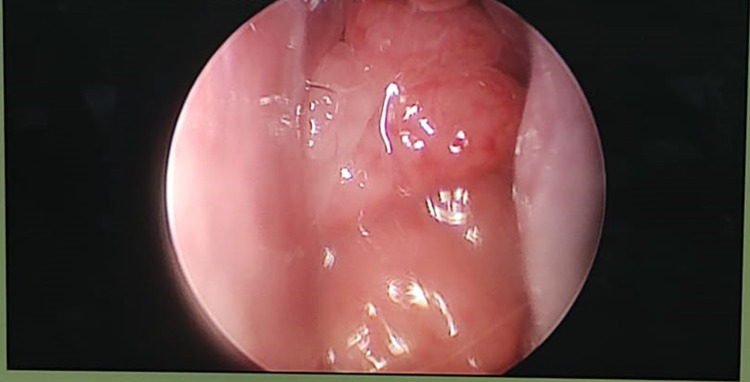

The study was performed on a total of 100 patients, in the department of Otorhinolaryngology, at Chettinad Hospital and Research institute, Chettinad academy of research and education, after getting approved by the Ethical Committee of the Chettinad University. A standard anaesthetic protocol was used for all the patients. After General anaesthesia, the usual physiologic parameters (respiratory rate, pulse rate, blood pressure, and temperature) were monitored during surgery. Standard surgical techniques were performed. Intra-operatively mucosa from nasal and paranasal sinuses, tonsils, and adenoid tissue was collected aseptically for bacteriological investigation (Figs. 1, 2, 3). Patients were extubated and shifted to the postoperative ward.

Fig. 2.

Bilateral tonsils in the oropharynx